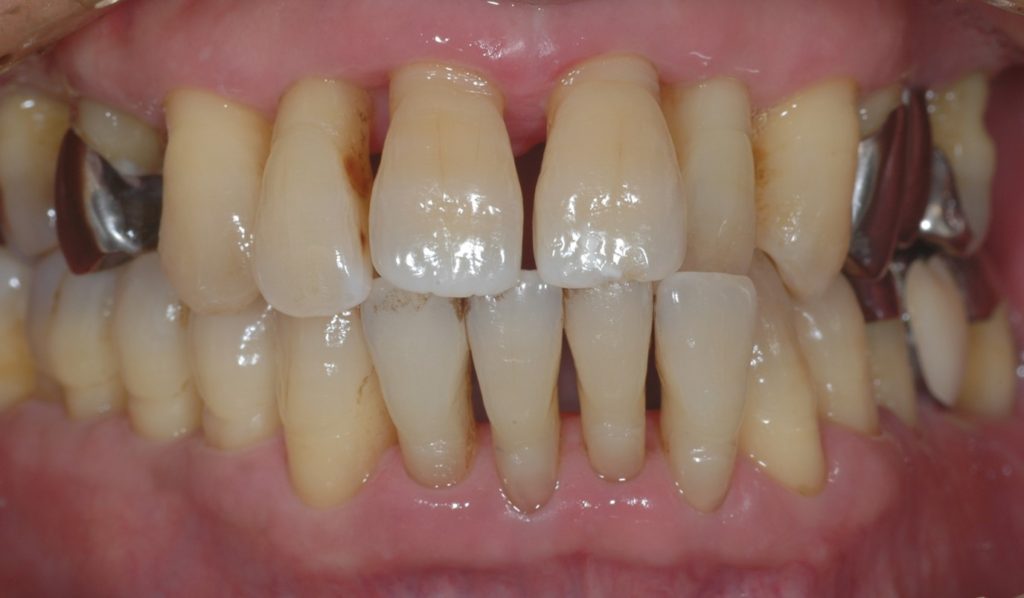

まだ治療途中ですが、下写真のように変化しました。

プラークや歯石が取り除かれ、歯肉の炎症が改善しました。また、上前歯の隙間が小さくなったのがわかります。

病的に歯が動き歯の位置が変化しても、歯周病治療をしていくと歯が本来あった位置に戻っていくことがよくあります。咬み合わせを調整したわけでもなく、矯正治療を行ったわけでもありません。歯周病治療によって炎症が改善した結果、正しい位置に歯が移動したものと考えられます。